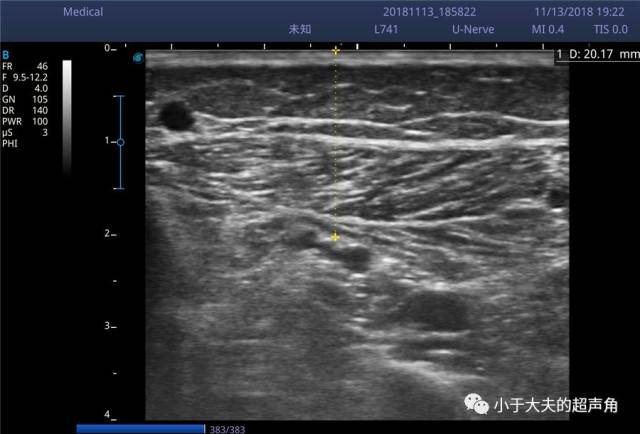

胫前胫后静脉超声图像

胫前胫后静脉超声图像,正常肺静脉超声图像